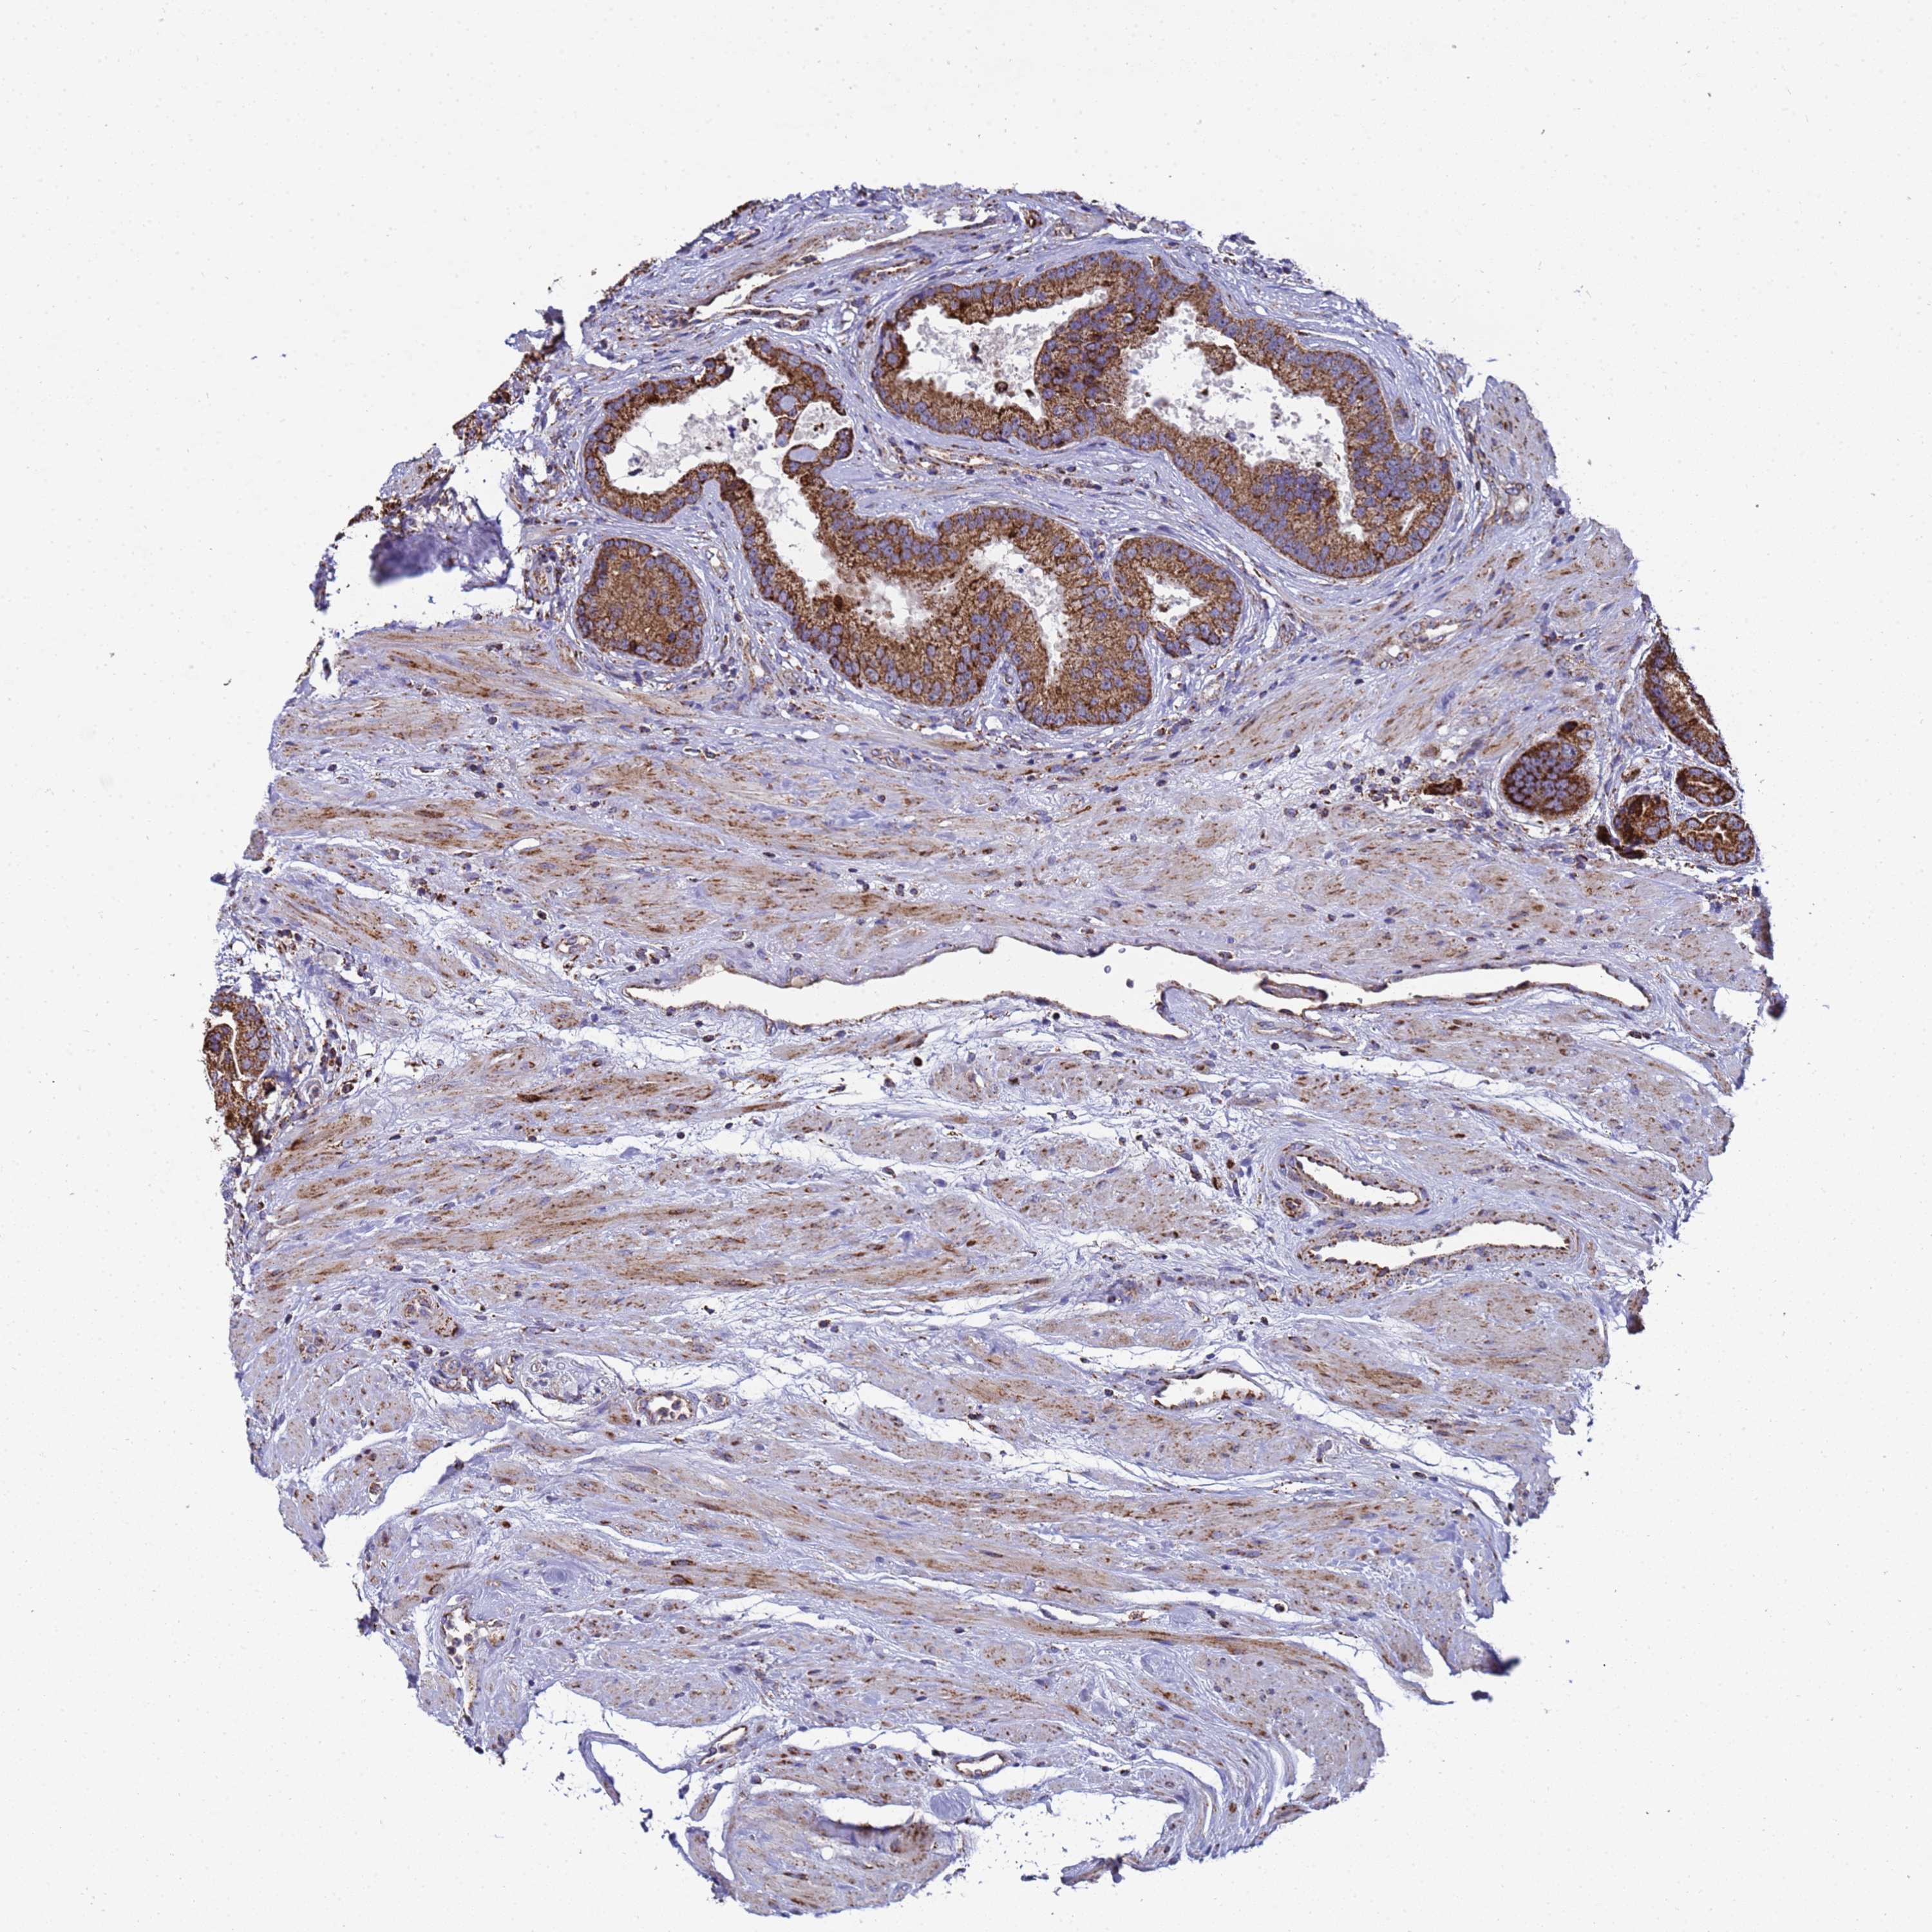

PROSTATE CANCER - Protein expressioni

A mouse-over function shows sample information and annotation data. Click on an image to view it in a full screen mode. Samples can be filtered based on level of antibody staining by selecting one or several of the following categories: high, medium, low and not detected. The assay and annotation is described here.

Antibody stainingi

Antibody staining in the annotated cell types in the current human tissue is reported as not detected, low, medium, or high, based on conventional immunohistochemistry profiling in selected tissues. This score is based on the combination of the staining intensity and fraction of stained cells.

Each image is clickable and will lead to virtual microscopy that enables deeper exploration of all samples and also displays staining intensity scores, fraction scores and subcellular localization as well as patient and tissue information for each sample.

Antibody HPA046775

Antibody HPA050633

Staining

High

Medium

Low

Not detected

Intensity

Strong

Moderate

Weak

Negative

Quantity

>75%

75%-25%

<25%

None

Location

Nuclear

Cytoplasmic/membranous

Cytoplasmic/membranous,nuclear

Adenocarcinoma, NOS

Adenocarcinoma, High grade

Adenocarcinoma, Low grade